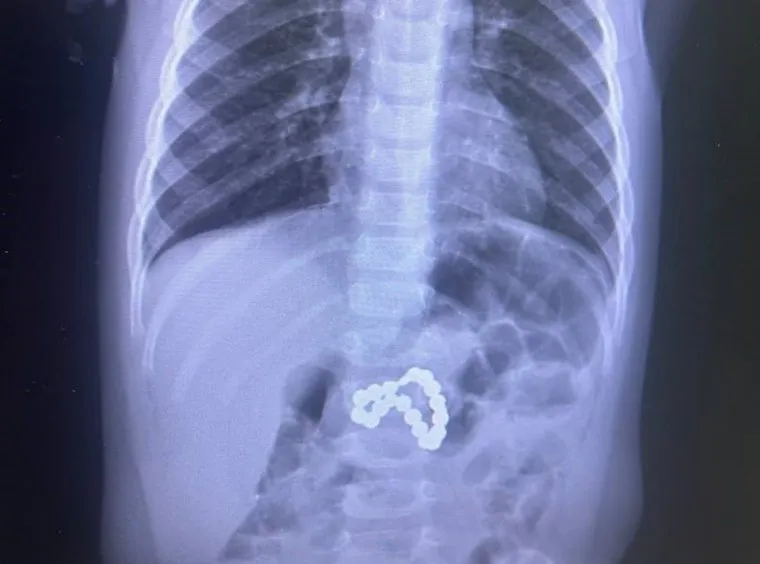

Врачи сургутского перинатального центра спасли жизнь девочке, проглотившей магниты. Ребенку пришлось провести экстренную эндоскопию, сложную операцию и переливание крови. Об этом в своем telegram-канале сообщила президент центра Лариса Белоцерковцева.

«Девочка поступила в тяжелом состоянии из-за проглоченных магнитов, которые вызвали перфорацию желудка и кишечника. Путь к выздоровлению был непростым: экстренная эндоскопия, сложная операция, ушивание перфорации, реанимация и переливание крови. Наши врачи боролись за жизнь девочки день и ночь», — рассказала Белоцерковцева.